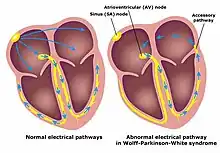

Wolff–Parkinson–White syndrome (WPWS) is a disorder due to a specific type of problem with the electrical system of the heart involving an accessory pathway able to conduct electrical current between the atria and the ventricles, thus bypassing the atrioventricular node.[2][3] About 60% of people with the electrical problem developed symptoms,[5] which may include an abnormally fast heartbeat, palpitations, shortness of breath, lightheadedness, or syncope.[1] Rarely, cardiac arrest may occur.[1] The most common type of irregular heartbeat that occurs is known as paroxysmal supraventricular tachycardia.[1]

The cause of WPW is typically unknown and is likely due to a combination of chance and genetic factors.[2] A small number of cases are due to a mutation of the PRKAG2 gene which may be inherited in an autosomal dominant fashion.[2] The underlying mechanism involves an accessory electrical conduction pathway between the atria and the ventricles.[1] It is associated with other conditions such as Ebstein anomaly and hypokalemic periodic paralysis.[1] The diagnosis of WPW occurs with a combination of palpitations and when an electrocardiogram (ECG) show a short PR interval and a delta wave.[3] It is a type of pre-excitation syndrome.[3]

Individuals with WPW have an accessory pathway that communicates between the atria and the ventricles, in addition to the AV node.[6] This accessory pathway is known as the bundle of Kent. This accessory pathway does not share the rate-slowing properties of the AV node and may conduct electrical activity at a significantly higher rate than the AV node. For instance, in the example above, if an individual had an atrial rate of 300 beats per minute, the accessory bundle may conduct all the electrical impulses from the atria to the ventricles, causing the ventricles to contract at 300 beats per minute. Extremely rapid heart rates such as this may result in hemodynamic instability or cardiogenic shock. In some cases, the combination of an accessory pathway and abnormal heart rhythms can trigger ventricular fibrillation, a leading cause of sudden cardiac death.

Bundle of Kent

The bundle of Kent is an abnormal extra or accessory conduction pathway between the atria and ventricles that is present in a small percentage (between 0.1 and 0.3%) of the general population.[10][11][12] This pathway may communicate between the left atrium and the left ventricle, in which case it is termed a "type A pre-excitation", or between the right atrium and the right ventricle, in which case it is termed a "type B pre-excitation" in old, currently abandoned classification.[13] Problems arise when this pathway creates an electrical circuit that bypasses the AV node. The AV node is capable of slowing the rate of conduction of electrical impulses to the ventricles, whereas the bundle of Kent lacks this capability. When an aberrant electrical connection is made via the bundle of Kent, tachydysrhythmias may therefore result.